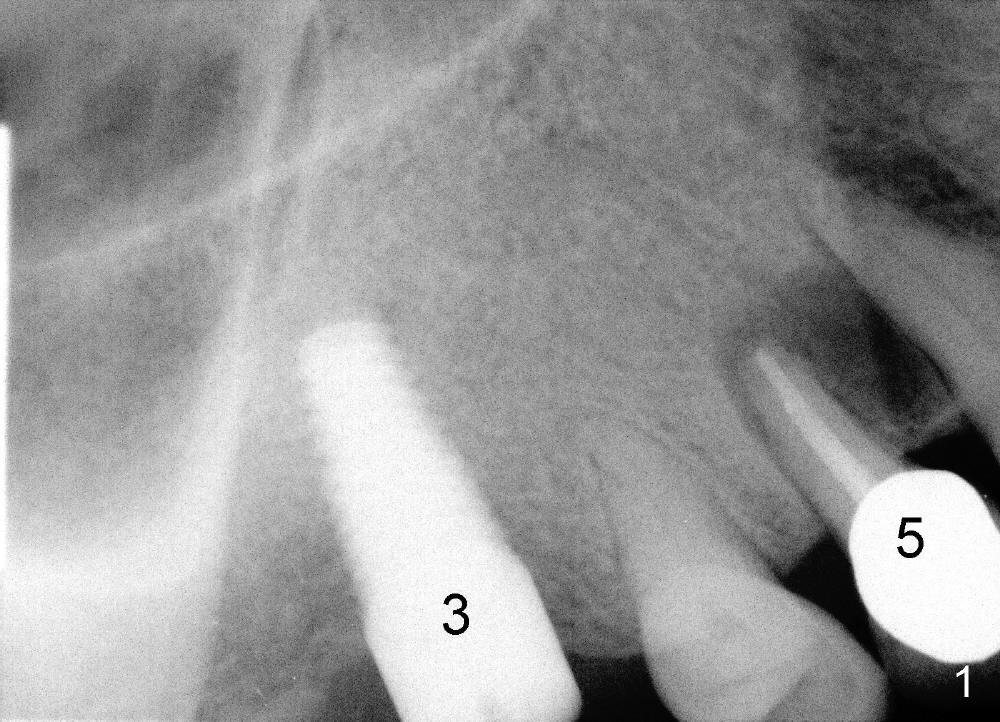

A 42-year-old man has poor dentition with missing multiple teeth. He was a smoker. After smoke cessation, two implants are placed at the sites of #3 (6x17mm) and 19 (5x14mm) (Fig.1,2). It does not sound great to place #3 implant close to a potential infection site (#5, Fig.1). But the latter is asymptomatic. Four months post #3 implantation, he returns with pain in the upper right sextant (Fig.3). The tooth #18 appears to shift mesially (Fig.4). To place a crown over #19 implant, the mesial surface of the crown of #18 has to be trimmed. What cannot be done associated with #18 shifting is food impaction between #17 and 18 (Fig.8). Clinical exam reveals crack of the tooth #4. Immediate implant is planned. Is it too close to the infection site?